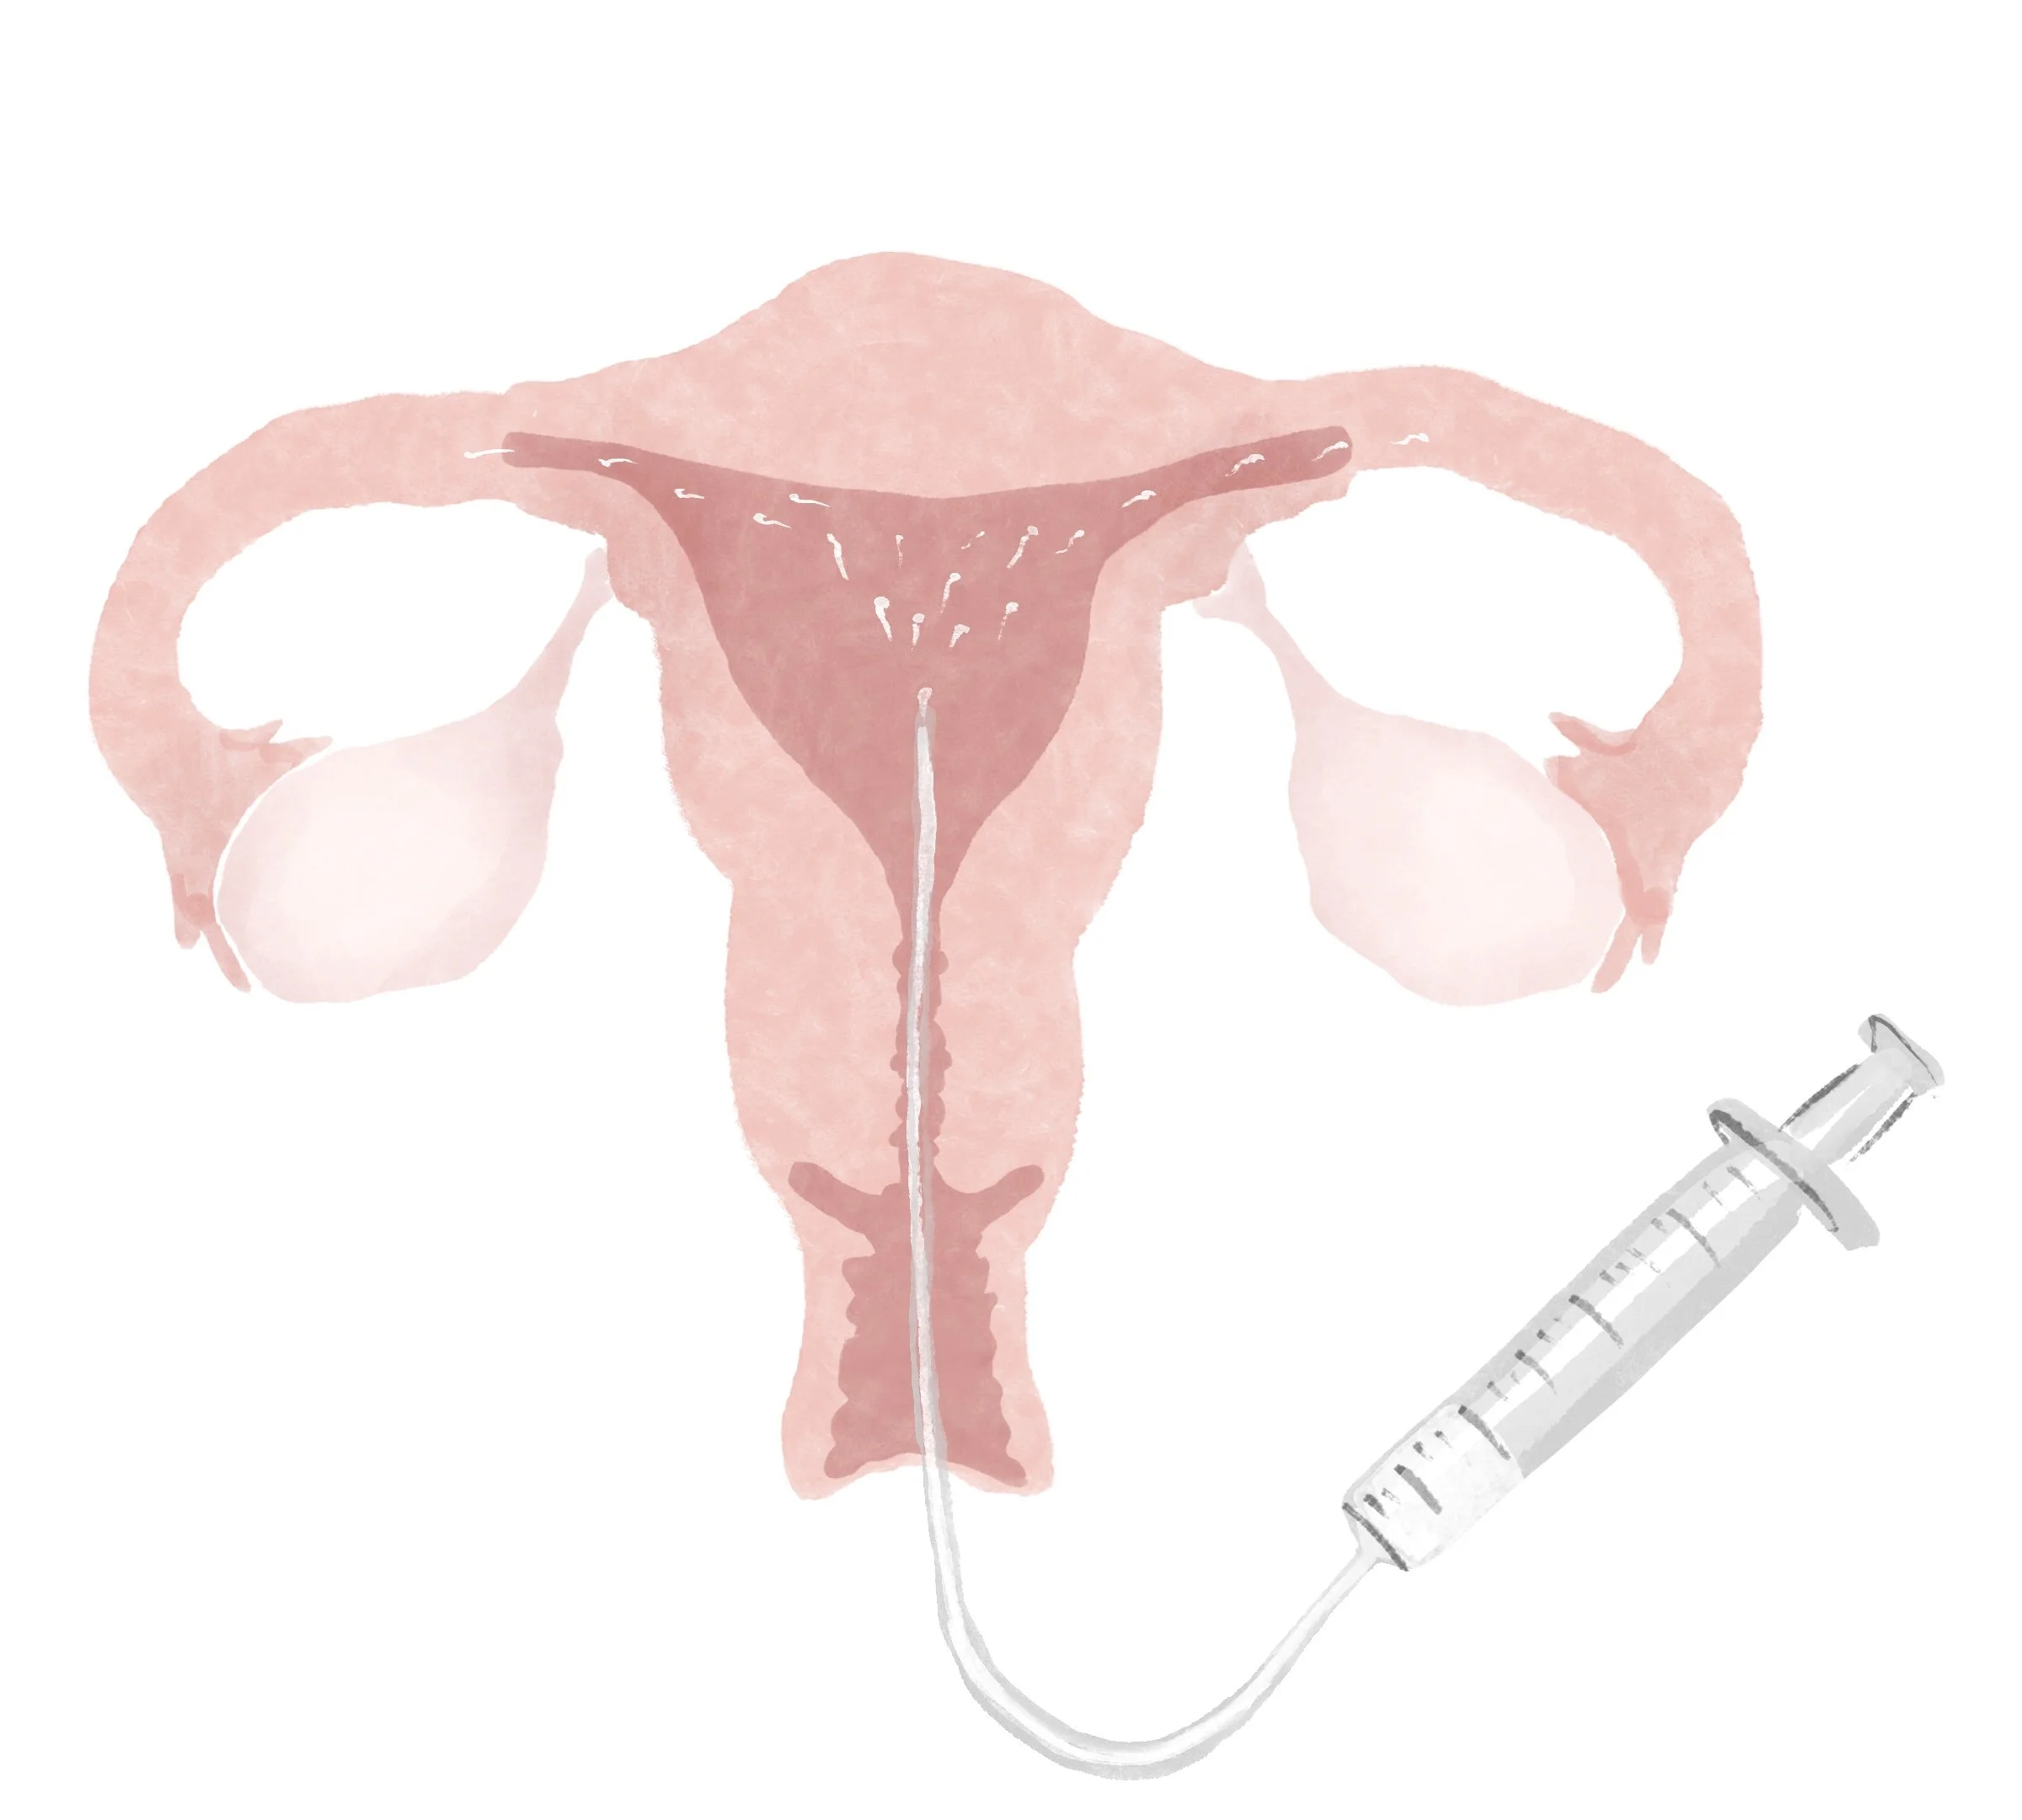

Intrauterine insemination (IUI)